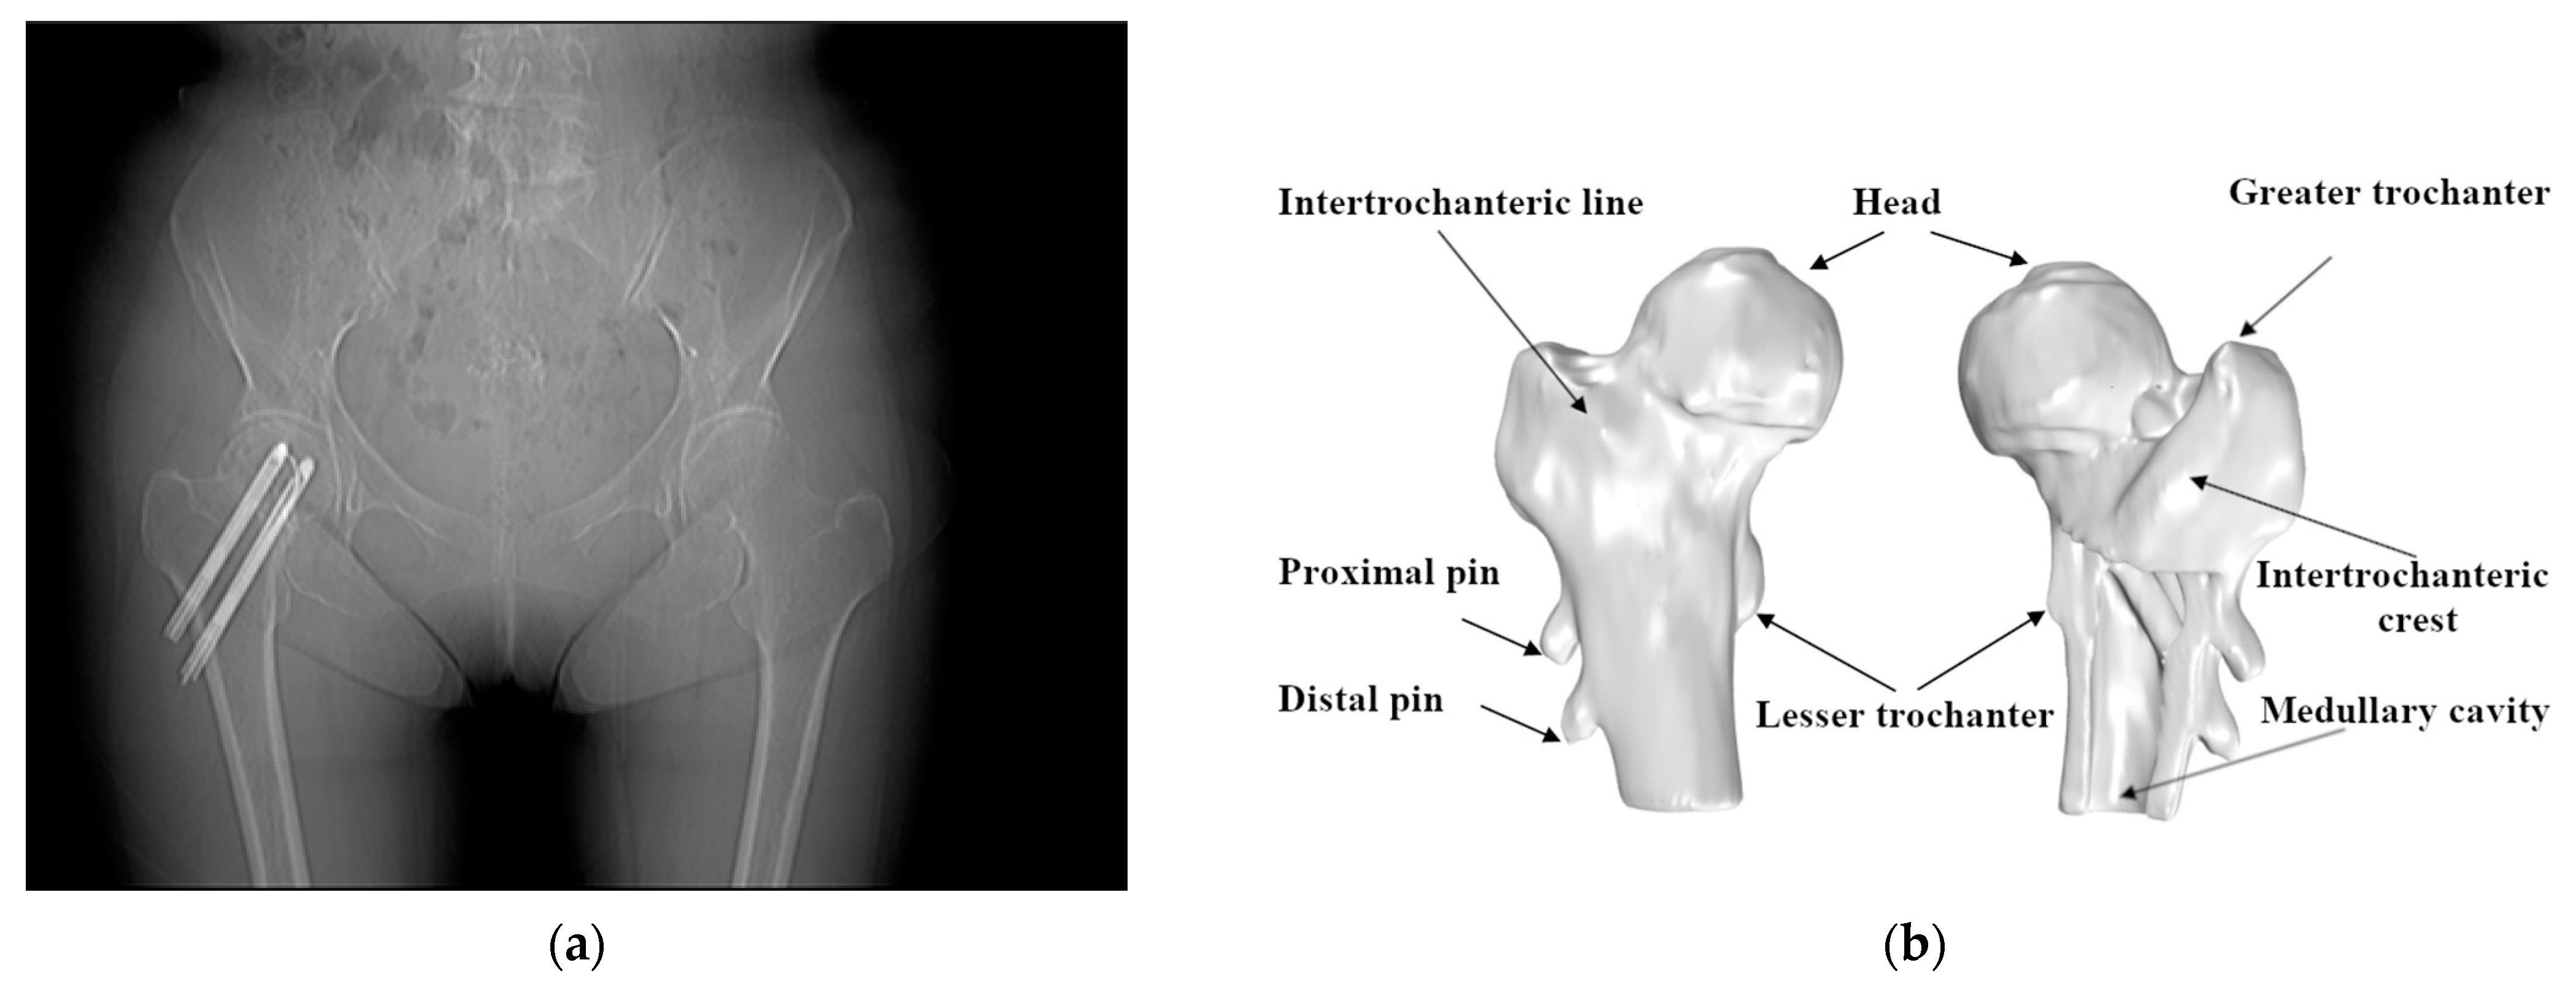

Due to the lack of periosteum and limited callus formation, the processing of healing is slow. Among the cases in this research, the Hansson pin (Hansson Pin System, Stryker) [18] was used to fix the femur’s neck. The Hansson pin is a 6.5-mm diameter unthreaded nail with various specifications and has a length ranging from 70 mm to 120 mm. Each pin can be divided into two parts, the outer sleeve and the inner movable hook pin. Typically surgeons use two pins for fixing and screwing out the hook pins when fixing (Figure 2).

Figure 2. Use of the Hansson pin for the fixation of femoral neck fractures: (a) the anteroposterior/posteroanterior X-ray (AP X-ray) of intracapsular fracture fixation using two Hansson pins; (b) the position of the Hansson pins in the anatomy of the femur.